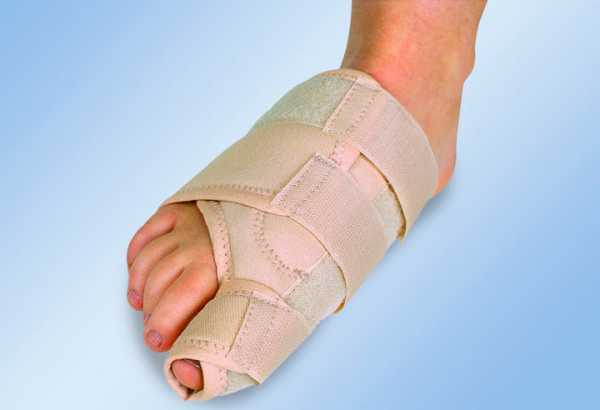

Ортопедические приспособления

В качестве консервативных мер, направленных на выправление деформированной стопы, рекомендуют использовать специальные ортопедические приспособления. К таковым относят:

- стяжки;

- стельки;

- ночной корректор;

- ортопедическая шина.

Лечебные стельки изготавливают для каждого пациента индивидуально. Они направлены на снятие основной нагрузки с больного сустава и на возвращение стопе амортизирующих свойств.

Для выравнивания фаланги пальцев и уменьшения угла деформации применяют специальные супинаторы и перегородки. Обычно используют ночной корректор, который позволяет удержать большой палец в правильном положении.

Ночной бандаж

Для постоянного ношения изобретены ортопедические шины, которые позволяют зафиксировать смещенный палец в неподвижном состоянии и со временем выравнивают форму стопы.

Ортопедическая шина, которую можно носить постоянно